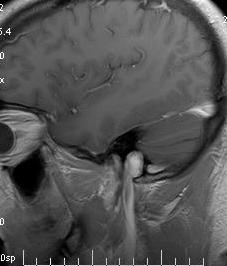

endobj /Type /Font Background and Purpose The magnetic resonance imaging in multiple sclerosis (MAGNIMS) group recently proposed guidelines to replace the existing dissemination-in-space criteria in McDonald 2010 magnetic resonance imaging (MRI) criteria for diagnosing multiple sclerosis. The Ependymal "Dot-Dash" Sign: An MR Imaging Finding of Early Multiple Sclerosis, AJNR Am J Neuroradiol 26:20332036, September 2005, "New diagnostic criteria for multiple sclerosis: Guidelines for research protocols", Lesional demyelinations of the central nervous system, Experimental autoimmune encephalomyelitis, Leukoencephalopathy with vanishing white matter, Megalencephalic leukoencephalopathy with subcortical cysts, Transfusion-associated graft versus host disease, https://en.wikipedia.org/w/index.php?title=Poser_criteria&oldid=1050248552, Articles with unsourced statements from October 2021, Articles with unsourced statements from January 2019, Creative Commons Attribution-ShareAlike License 3.0, Two attacks and one evidence (clinical or paraclinical), Attack: Occurrence of a symptom of neurological dysfunction for more than 24 hours, Clinical evidence: Neurological dysfunction demonstrable by neurological examination, Paraclinical evidence: Demonstration by any test of the existence of a non-clinical lesion in the CNS, CDMS Clinically definite MS. 1908 [940] endobj